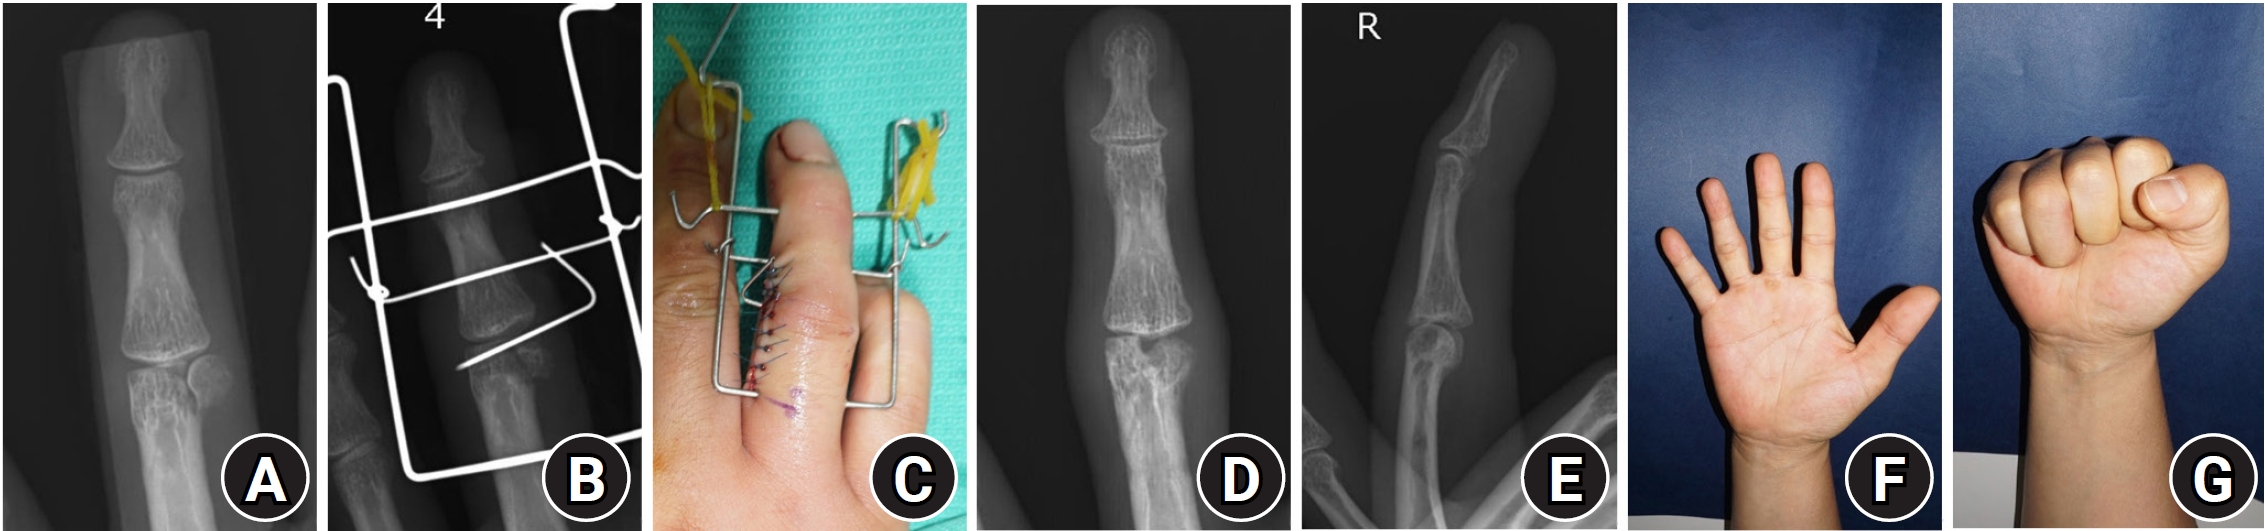

Fractures of the base of the distal phalanx most commonly present as bony mallet finger, where the proximal fragment displaces dorsally. Bony mallet finger occurs when strong axial compression or flexion forces act on the DIP joint while the PIP joint remains extended, causing the proximal fragment, where the extensor tendon inserts, to displace dorsally [21]. A relatively rare mechanism of injury involves hyperextension of the DIP joint, leading to a dorsal impaction of the distal phalanx articular surface against the head of the middle phalanx. In such cases, the remaining distal phalanx may easily dislocate palmarly, often requiring surgical treatment. If left untreated, a bony mallet finger may progress to compensatory hyperextension of the PIP joint, resulting in a swan-neck deformity, or cause joint stiffness or posttraumatic arthritis due to intraarticular fractures. Conservative treatment may be considered when there is no displacement of the bone fragment, less than 30% involvement of the articular surface, and no subluxation of the joint. If the fracture involves 30%‒50% or more of the articular surface, instability may occur [22]. Okafor et al. [23] reported on 31 patients with bony mallet fingers treated conservatively, and found that 48% developed arthritis, 29% developed a swan-neck deformity, and an average of 8.3° of DIP joint drooping; however, most patients had satisfactory outcomes. The Cochrane Review also found no significant difference between conservative treatment and K-wire fixation [24]. However, Niechajev [25] recommended surgical treatment when the bone fragment exceeds 3 mm or there is subluxation of the DIP joint. Surgical treatment is most commonly performed using extension block K-wire fixation, first proposed by Ishiguro et al. [26] in 1988 and later modified by various surgeons. Modified techniques include using two extension block pins to equally prevent the extension of the fractured bone fragments [27], or passing a pin through the DIP joint in a diagonal direction or from the palmar side rather than from the fingertip to facilitate fixation [28]. Direct fixation of the bone fragment has also been attempted [29], and methods using dorsal metal pins for fracture reduction and fixation have been introduced (Fig. 1) [30]. While open reduction and other devices, such as small screws, hook plates, or pull-out sutures, have been explored, these techniques are still used sparingly, and there is limited evidence to support their primary use [31].

Fig. 1.

Modified extension block pinning technique. One or two extension blocking pins are inserted from the dorsal aspect of the proximal phalanx head at around a 45° angle to prevent dorsal fragment displacement (A). Although the distal phalanx segment is extended, the reduction is not perfect (B). With the aid of a dorsal counterforce reduction Kirschner wire (K-wire), an axial transarticular K-wire is inserted from the volar aspect of the distal phalanx (C, D). A dorsal counterforce K-wire is additionally inserted to fix the dorsal fragment in addition to the conventional extension block technique (E).

Fig. 1. Modified extension block pinning technique. One or two extension blocking pins are inserted from the dorsal aspect of the proximal phalanx head at around a 45° angle to prevent dorsal fragment displacement (A). Although the distal phalanx segment is extended, the reduction is not perfect (B). With the aid of a dorsal counterforce reduction Kirschner wire (K-wire), an axial transarticular K-wire is inserted from the volar aspect of the distal phalanx (C, D). A dorsal counterforce K-wire is additionally inserted to fix the dorsal fragment in addition to the conventional extension block technique (E).